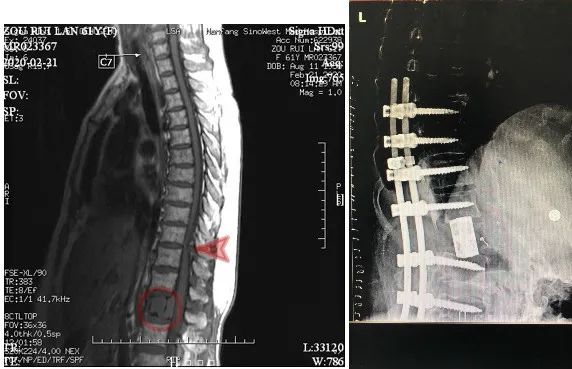

今年2月份,周阿姨突然出现排尿困难,足底发麻的情况,实在难以忍受便在当地医院做了检查,结果提示腰椎肿物。于是慕名来到我院就诊。

阅读次数:4734